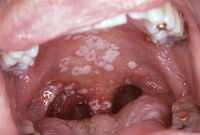

HIV ინფექცია

პერორალური კანდიდოზი აივ-ით ინფიცირებულ პაციენტებში